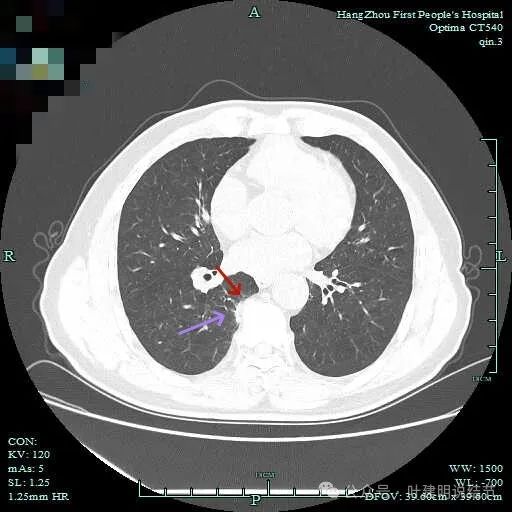

其他病灶情况:

右下脊柱旁怎么也像有磨玻璃结节?但此处正常CT也是略显有慢性炎似的征象的,可这个病人明显结节状,还表面有细毛刺似的。

次病灶连续层面观察:

紧贴脊柱处混合密度,趴在脊柱上,这不像结节状。

但有小血管似的,磨玻璃部分界限较清。但此类异常影像在正常人的CT上也挺常见。

密度较高,确实像血管进入。但病灶片状,趴在脊柱上。